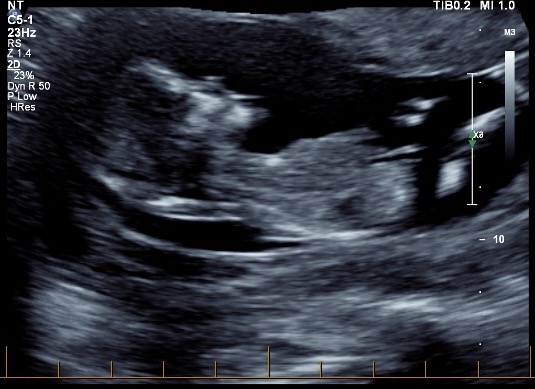

Hi all! I'd love some opinions here, I'm not even sure if there's a nub to see in any of these pictures. These were taken at exactly 13 weeks. I'm now 19 weeks and still have 1 week and 6 days until my anatomy scan (not that I'm counting or anything!) I have three boys and this is my last baby, so I'd love a little girl! Thanks in advance if anyone can help!

Attachment 35249